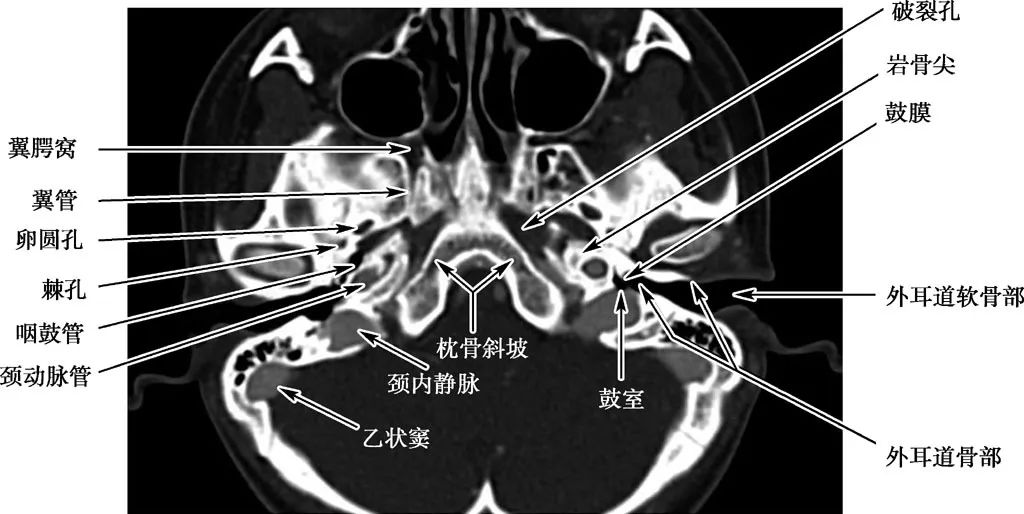

耳部及其周围的重要解剖结构 (CT横断面)

A.上骨半规管层面;B.外骨半规管层面;C.前庭窗层面;D.耳蜗层面;E.颈动脉管层面1.上骨半规管;2.弓形下窝;3.总骨脚;4.后骨半规管;5.外骨半规管;6.内耳道;7.耳蜗;8.面神经管迷路段;9.膝状神经节;10.前庭;11.上鼓室;12.乳突窦入口;13.乳突窦;14.鼓膜张肌;15.锤骨头;16.砧骨体;17.前庭窗;18.前庭导水管;19.圆窗;20.鼓岬;21.锤骨颈;22.砧骨长脚;23.面神经隐窝;24.锥隆起;25.鼓室窦;26.颈动脉管;27.咽鼓管;28.耳蜗导水管;29.颈静脉球